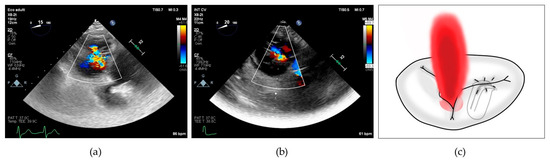

To better characterize this last concept, we collected the prevalence of posterior grasping needed in our population. Jet localizations were divided in 4 categories: isolated central when the prevalent jet was central, isolated antero-septal (AS) when the prevalent jet was located between anterior and septal leaflets, central + AS when both components coexisted and neither one was prevalent on the other, and finally, we included in a last category named as “complex” all the jet localizations which cannot be included in the others, encompassing regurgitation characterized by multiple jets located in the posterior commissures and star-shaped jets (see Figure 2).

Figure 2. (a) 2D transesophageal echocardiographic transgastric view showing complex tricuspid regurgitation; (b) 2D transesophageal echocardiographic transgastric view showing central + anterior–septal tricuspid regurgitation; (c) drawing showing residual tricuspid regurgitation between anterior and posterior leaflets after implantation of a single clip grasping anterior and septal leaflet.